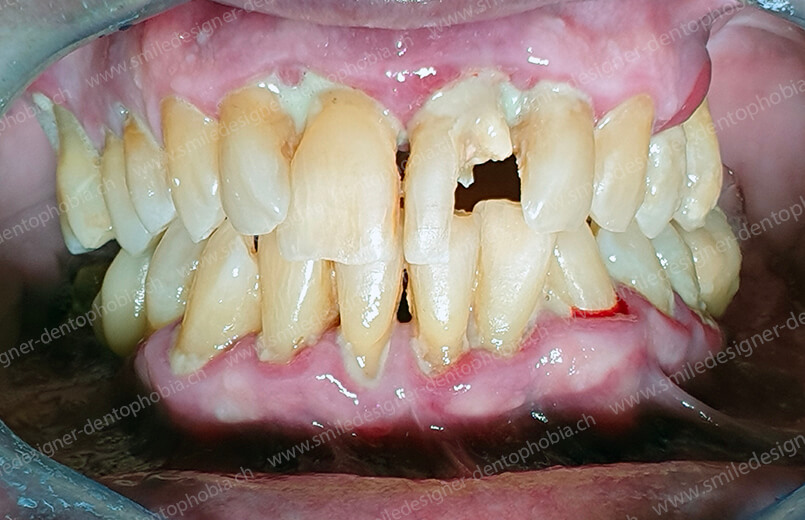

Cas clinique « DOMINO SURGERIES MCI » : Bridge implanto-porté sans extension postérieure (ALL ON 10/8). Version définitive des bridges avec un cosmétique en céramique. Double comblements de sinus et double greffes osseuses d’apposition pour la reconstruction du maxillaire.

Cas clinique « DOMINO SURGERIES MCI » : Bridge implanto-porté sans extension postérieure (ALL ON 8/6). Version définitive des bridges avec un cosmétique en céramique. Double comblements de sinus et double greffes osseuses d’apposition pour la reconstruction du maxillaire.

Cas clinique « DOMINO SURGERIES MCI » : Bridge implanto-porté avec extensions postérieures (ALL ON 6/6).